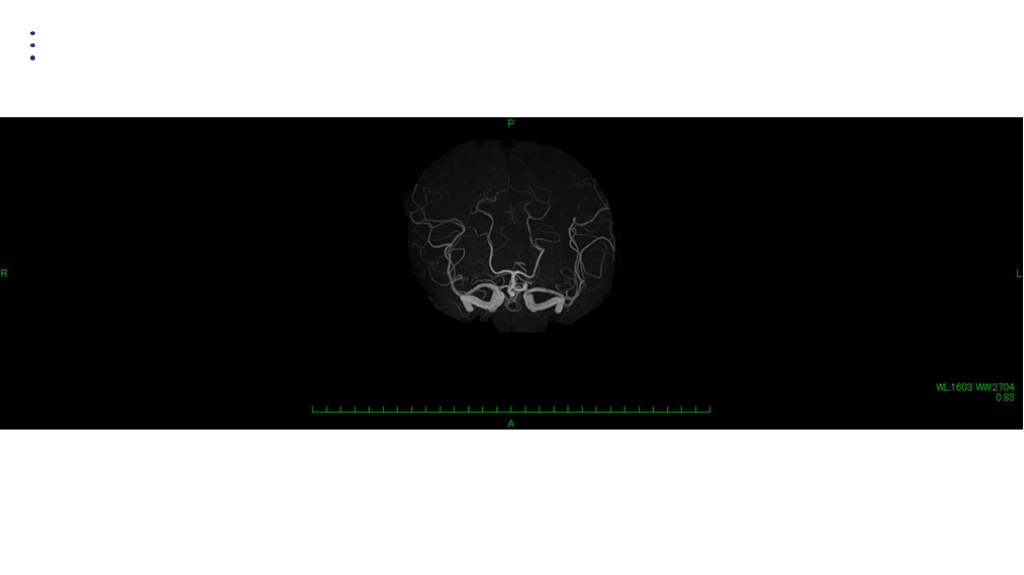

画像 所見 DAY 30 MRA 改善

UPTODATE:Reversible cerebral vasoconstriction syndrome RCVSで臨床的に重要な事項のまとめ 最大の鑑別疾患である、くも膜下出血を十分鑑別する。 再発性のTCHを認める。数日間にわたるTCHの病歴になる。 誘発因子がある:オーガズム、運動、急性ストレス、バルサルバ負荷  (緊張、咳嗽、くしゃみ)、入浴、水泳 MRAでのSpasm所見はあとから顕在化する。発症時はわからないことがある。一週間以内には出現する、と理解しておく。よって、フォロー画像は3-5日後に実施する。spasm所見は3か月以内には回復する。 脳梗塞を認める場合もあり、留意が必要。